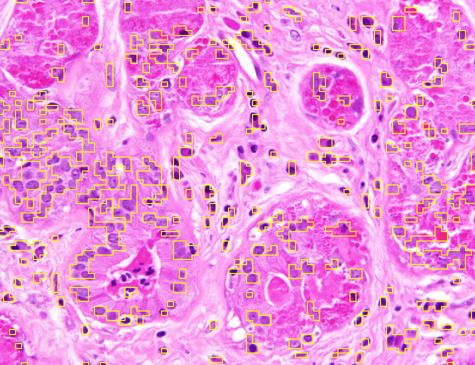

7.1.3 OT vs. Variance

To assess the contribution of the OT-based metric in isolation, we substituted the superpixel initialization with a uniform rectangular partition and compared the outcome to that of the SMST algorithm. Since SMST also employs an initial superpixel decomposition followed by minimum-spanning-tree merging and variance-based splitting, any discrepancies can be attributed solely to the choice of metric.

Figure 4 shows, in its first row, two representative images from Dataset 1, overlaid with uniform rectangular partitions of varying resolution. Since the task was to segment red cells, only the red channels of the images were provided to both models. The second row of the figure presents the segmentation results from SP. Despite the rectangular initialization, our approach captured foreground regions using the smallest boxes possible while adhering to the rectangle boundaries. The third row of Fig. 4 shows the SMST results, which detected fewer cells and, across all resolutions, tended to over-segment the background into multiple regions.

Figure 4: Comparison of OT-based segmentation and variance-based SMST. The first row (a–d) shows two images I1 and I2 from Dataset 1 partitioned into rectangular superpixels of sizes 40×40 (a), 30×30 (b), 80×80 (c), and 70×70 (d), respectively. The second row (e–h) shows SP results (times in seconds: 1.97, 0.28, 22.48, 16.12). The third row (i–l) shows SMST results (times in seconds: 0.35, 0.35, 0.37, 0.43).